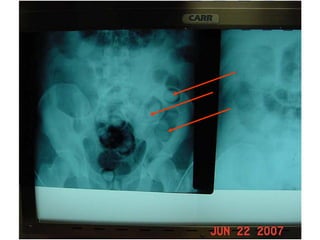

CÁPSULA CON COCAÍNA

CÁPSULAS CON COCAÍNA

CÁPSULAS CON COCAÍNA  ENTERAS